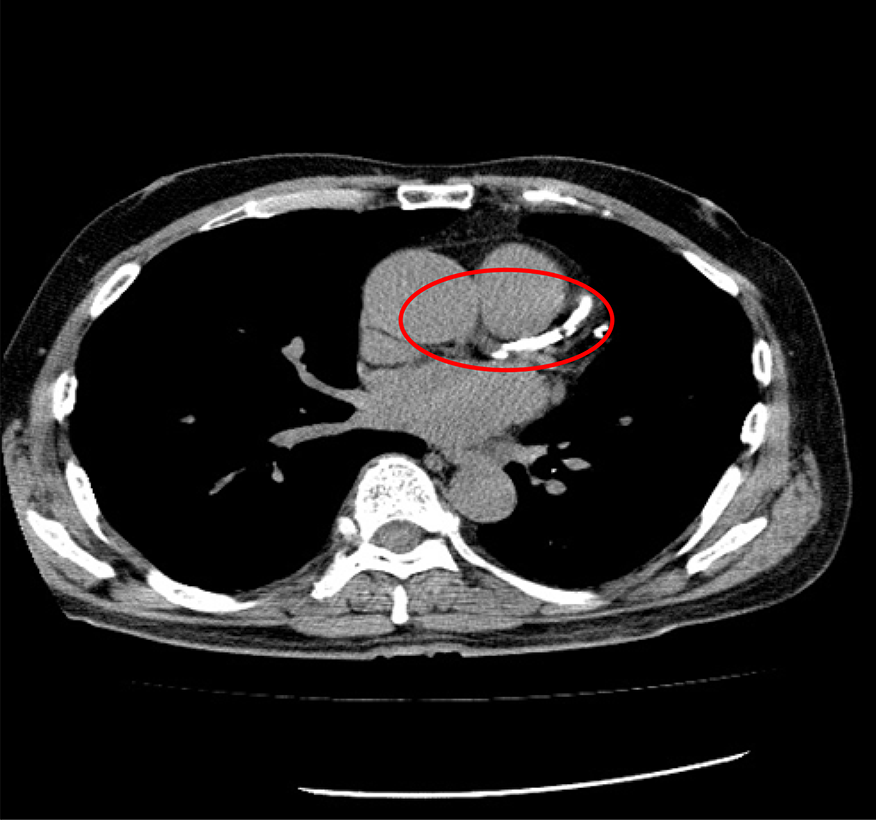

・冠動脈疾患(冠動脈石灰化病変)

心臓を栄養する血管である冠動脈の石灰化を測定するCT検査です。

胸部CTより少ない被ばく線量で造影剤を使わず、比較的簡便に心筋梗塞や狭心症のリスクを調べられる検査です。

冠動脈の石灰化は動脈硬化が進行し、血管の壁にカルシウムが沈着した状態です。石灰化が多いほど動脈硬化が進み心筋梗塞や狭心症のリスクが高くなります。

石灰化スコアCTで血管の状態を調べてみましょう。

石灰化が認められない血管

石灰化が認められる血管